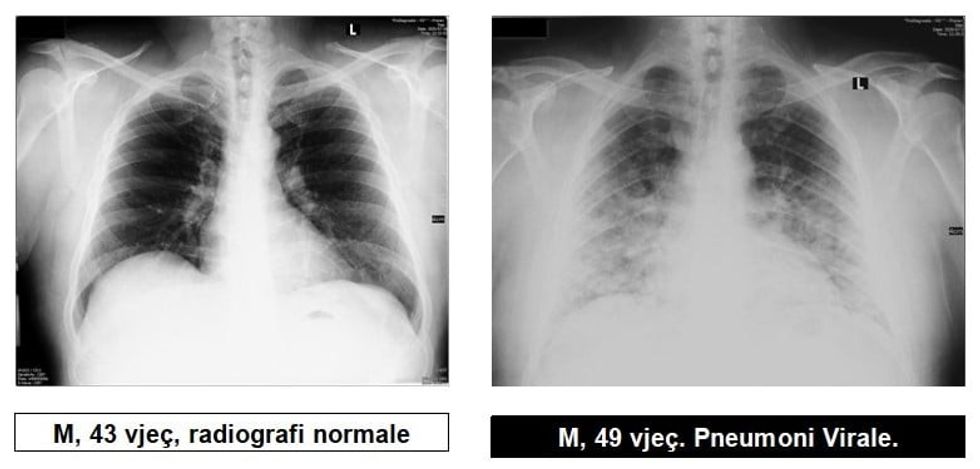

Radiologu në Spitalin Rajonal të Prizrenit, Sylejman Krasniqi tregon pamjet e mushkërive të pacientëve me pneumoni virale.

“Për te gjithë ata që maskat i kane veç si dekorim, për ata që distancën sociale e kanë diçka të huaj dhe për të gjithë ata që nuk i respektojnë këshillat e institucioneve relevante Shëndetësore, këto imazhe le të ju shërbejnë që ta kuptoni se megjithatë virus ka, pandemi ka dhe situata nuk është e mirë”, ka shkruar Krasniqi, përcjell Telegrafi.

Sipas Institutit Kombëtar të Shëndetësisë Publike të Kosovës, numri i rasteve aktive ka shkuar në 2 mijë e 995. Numri total i rasteve pozitive në Kosovë ka arritur në 6 mijë e 917 që nga 13 marsi kur u konfirmuan rastet e para.